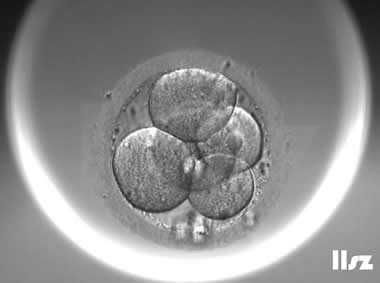

下面视频是胚胎在时差培养箱中培养至D3的整个过程,图片是D3(第68小时)的卵裂期胚胎图,本文D3胚胎评价是以D3时间点图片的形态学为依据,胚胎评级如下:

| Ⅰ级:该枚D3胚胎为8细胞,碎片不超过10%,因此评级为I级。 | |